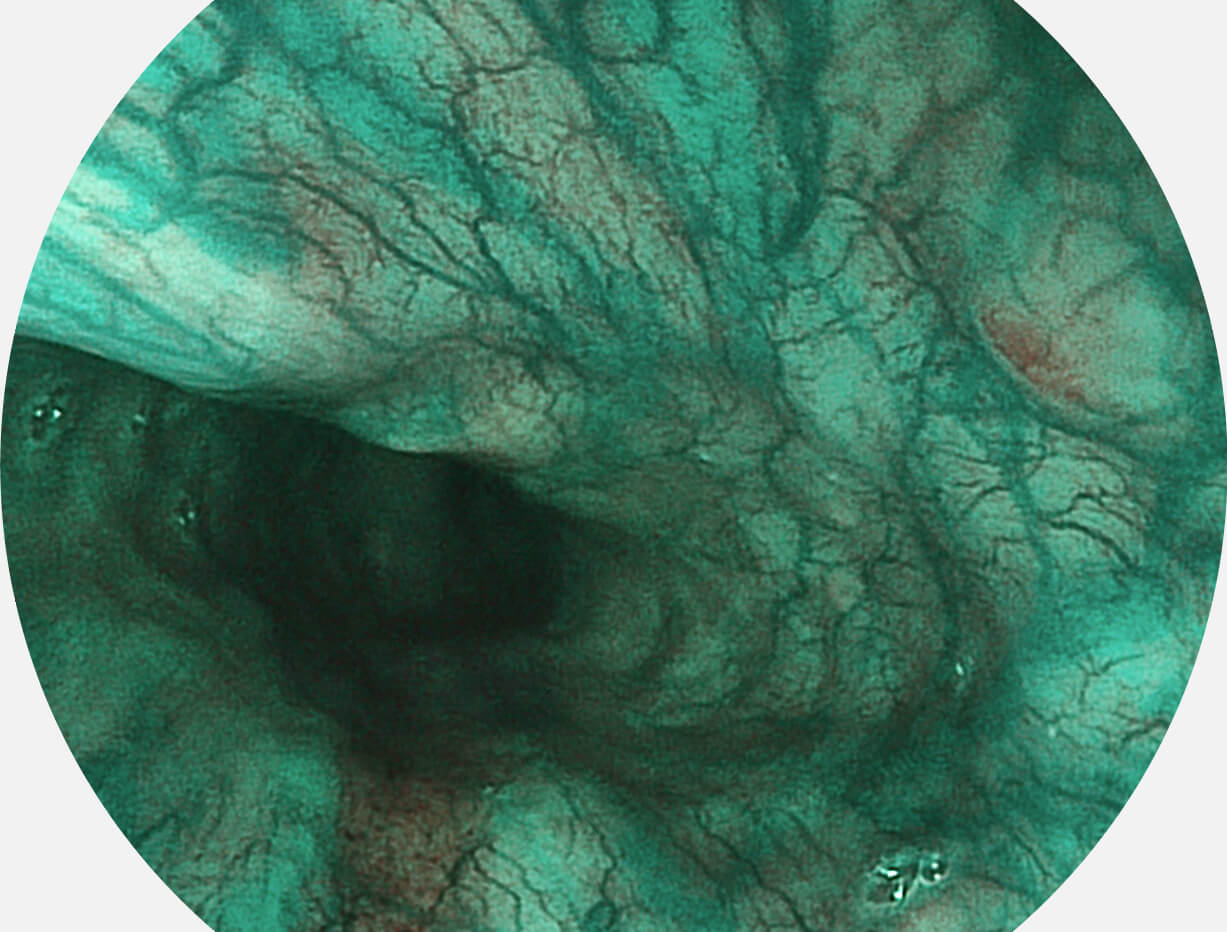

白光图像

VIST图像

强调浅层黏膜结构的同时,保证照明亮度和提升浅层微血管与中层血管颜色对比度,病变边界更清晰。

Versatile Intelligent Staining Technology, VIST